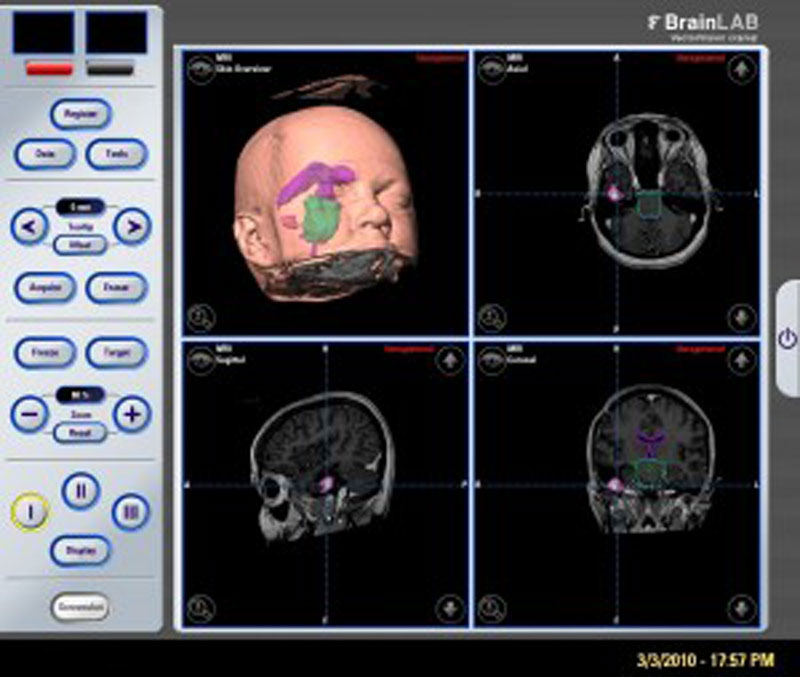

Нейрохирурги Пироговского Центра проводят апробацию первого русскоязычного протокола предоперационного картирования речи в клинической практике у пациентов с опухолями головного мозга и эпилепсией.

Отделению нейрохирургии Пироговского Центра исполнилось 8 лет. За это время его специалисты прооперировали около 10 тысяч пациентов. Ежегодное число операций за время работы отделения выросло с 400 до 2,5 тысяч в год. Здесь развивается несколько уникальных технологий и методов лечения пациентов с эпилепсией, опухолями головного мозга и дегенеративными заболеваниями позвоночника. Ежегодно около 400 пациентов с эпилепсией проходят предхирургическое обследование.

С 2021 г. в Лаборатории диагностики и лечения эпилепсии Отделения нейрохирургии стационара стали проводить радиочастотную термодеструкцию выявленных эпилептогенных очагов одновременно с проведением инвазивного стерео ЭЭГ мониторирования.

Пироговский Центр в сотрудничестве со Сколковским институтом науки и технологий, ООО «Сбермедии» и ООО «Иммерсмед» продолжил исследовать возможности применения цифровых инноваций в медицине. Ведутся проекты по использованию современных технологий, включая машинное обучение, для обработки результатов магнитно-резонансной томографии и электроэнцефалографии. Цель проекта — изучение причин и своевременная диагностика эпилепсии, что позволит не только приоткрыть тайны функциональных структур головного мозга, но и вовремя начать прием наиболее подходящих медикаментов, провести нейрохирургическую операцию, повысив тем самым вероятность полного излечения пациентов.

В Пироговском Центре создана соответствующая мировым требованиям эпилептологическая служба:

- Мультидисциплинарная команда (врачи разных специальностей, инженеры, лингвисты, математики и аналитики, специалисты IT)

- Высокотехнологичная нейрохирургическая служба

- Современная нейрофизиологическая лаборатория

- Передовая анестезиологическая служба

- Современная нейровизуализация (МРТ, ОФЭКТ, SISCOM)

Внедрен современный протокол диагностики эпилептогенных очагов головного мозга — протокол SISCOM (Subtraction Ictal SPECT Co-Registered to MRI)